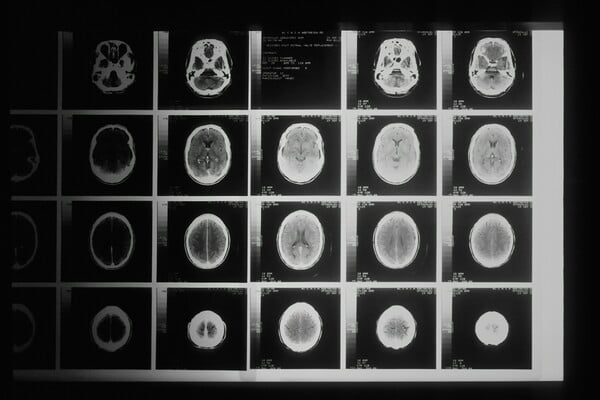

Η μηνιγγίτιδα είναι φλεγμονή των μεμβρανών που περιβάλλουν τον εγκέφαλο και τον νωτιαίο μυελό (οι μήνιγγες), η οποία προκαλείται από βακτήρια ή ιούς.